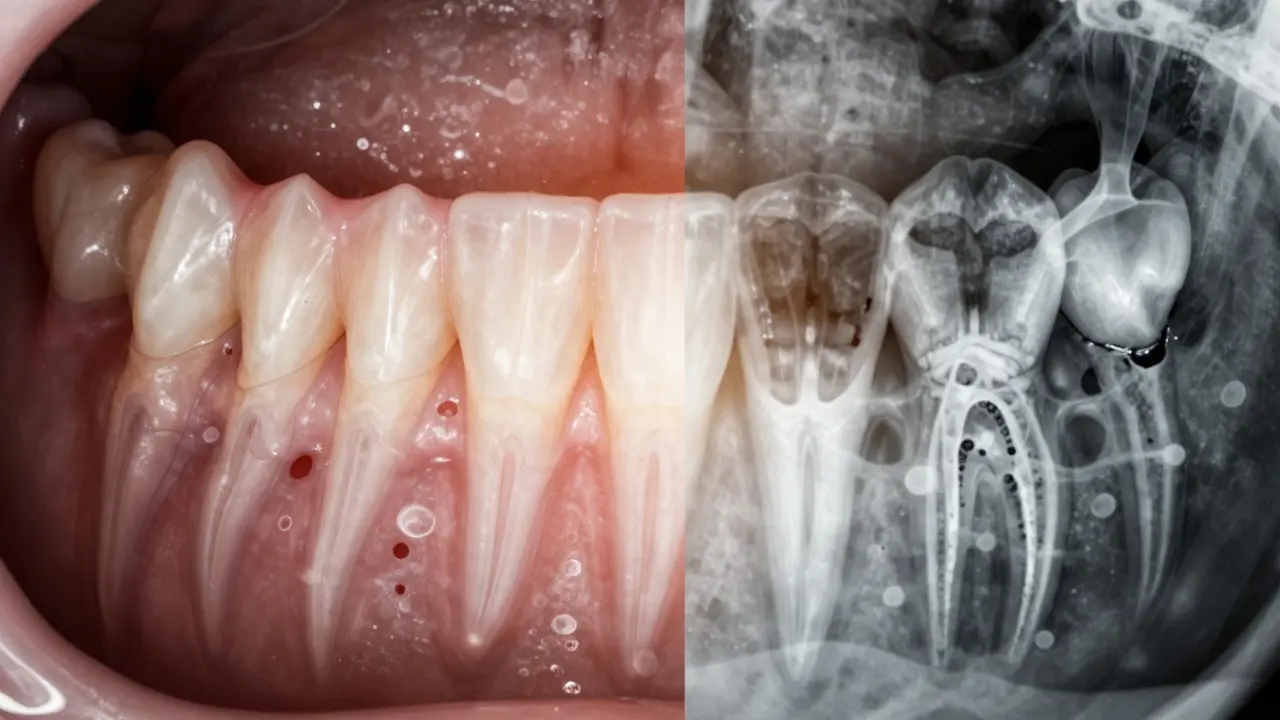

Na rentgenovém snímku se to projeví jako zúžení kosti kolem kořene zubu. V začínající fázi je to jen 1-2 mm ztráty. Zdá se to málo? Ale to je jako kdyby se vaše domácí základy začaly rozpouštět - o 1 milimetr ročně. Za pět let to znamená 5 cm. A u zubů to znamená, že zub už nemá dostatek podpory a může spadnout.

Mikroskopické bakterie ničí kost pod dásněmi, zánět se šíří jako kouř.

Porovnání zdravé a poškozené dásně a kosti v jedné kompozici.